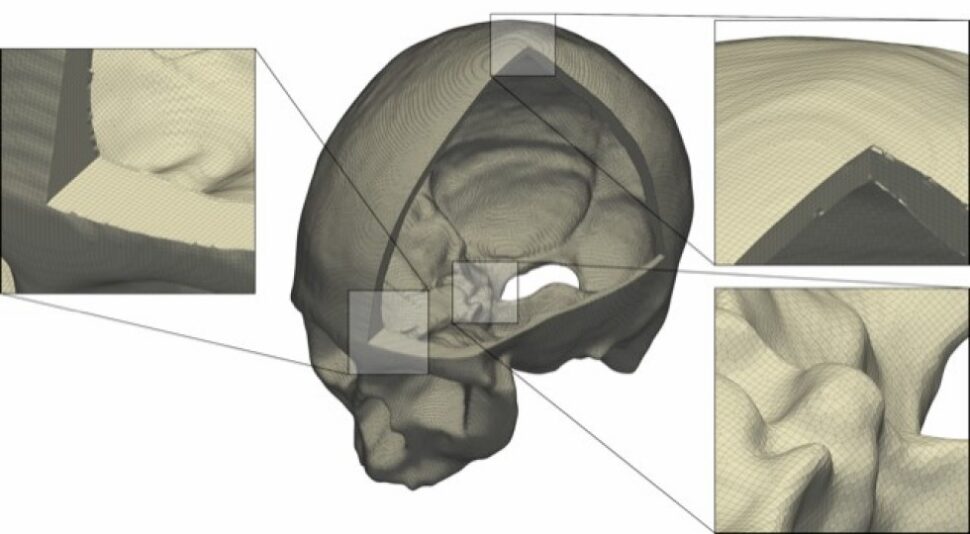

Foto: Patrick Marty/ETH Zürich